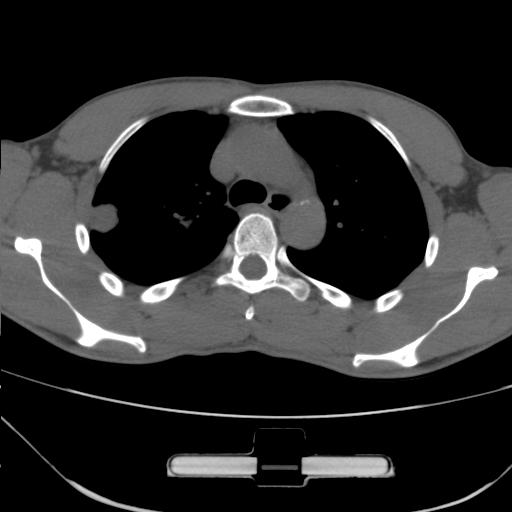

右肺上叶后段近胸膜下结节样异常密度灶,似见分页及毛刺,考虑右肺上叶周围型肺ca,建议穿刺病理检查

缺乏病史,症状体征,但这个孤立结节具备了几乎所有的恶性征象:分叶,毛刺,空泡征,胸膜凹陷征,血管集束。